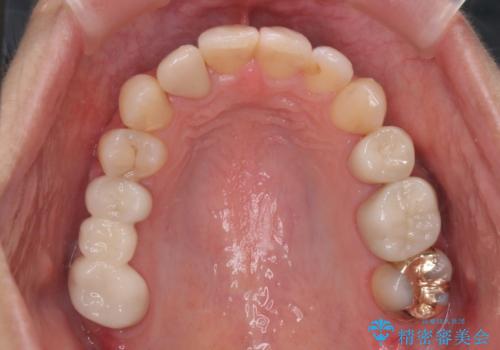

あきらめないで!!虫歯でボロボロでも大丈夫! 非抜歯矯正と虫歯、インプラント治療で見違える歯並びに。

②右上の親知らずは活かしてブリッジの支台にする

という、予算がかからないように歯を保存する治療計画を立てました。

途中矯正後に妊娠出産、育児等で2年以上中断を経た後虫歯治療の続きを行いました。最終的に治療完了まで行い状態は安定しています。